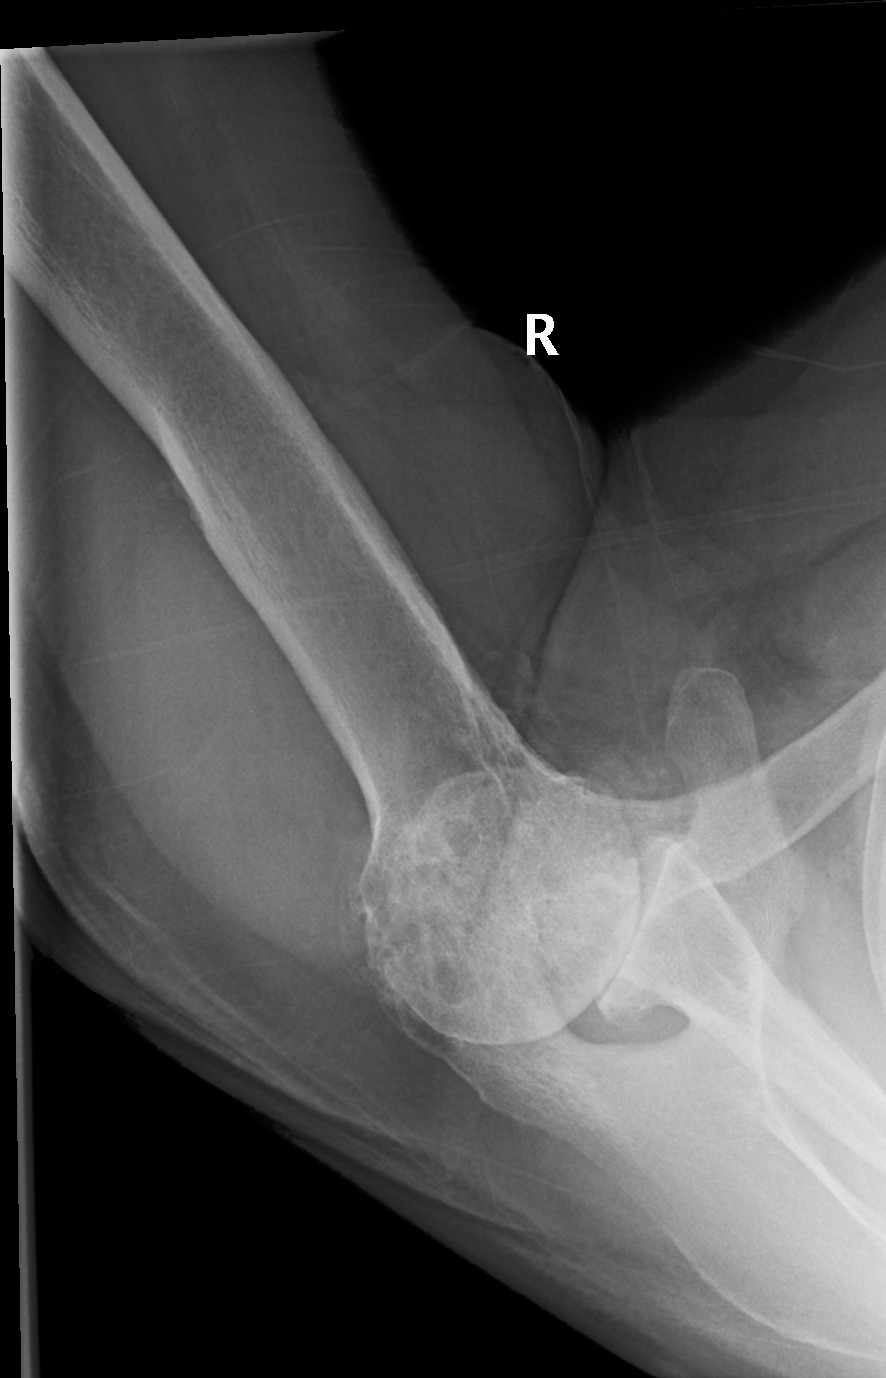

Rotator cuff tear arthropathy. (a) Conventional Xray, (b Rotator Cuff Tear Arthropathy Of Right Shoulder  Identify the risks and physical exam findings associated with a complete rotator cuff tear.   rotator cuff tear arthropathy is a spectrum of degenerative disease that develops due to a rotator cuff deficient shoulder. A rotator cuff tear is an injury to your rotator cuff that can cause shoulder pain and the inability to.   rotator cuff arthropathy is a. Rotator Cuff Tear Arthropathy Of Right Shoulder.